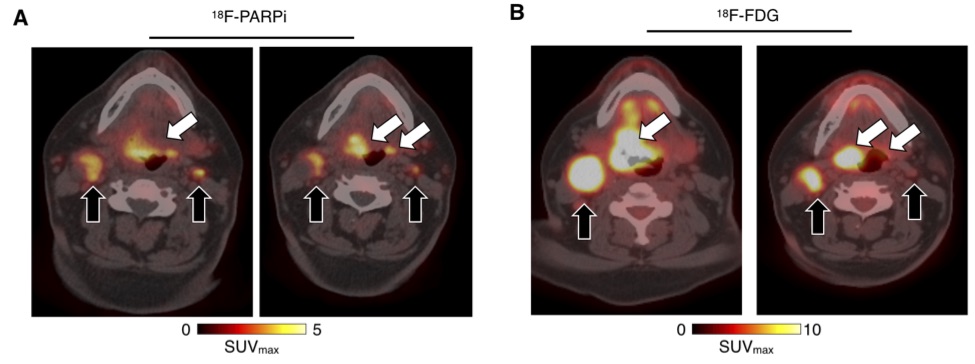

Results. 18F-PARPi was well-tolerated by all patients without any safety concerns. Of the 11 patients included in the analysis, 18F-PARPi had focal uptake in all primary lesions (n = 10, SUVmax = 2.8 ± 1.2) and all 18F-FDG positive lymph nodes (n = 34). 18F-PARPi uptake was seen in 18F-FDG negative lymph nodes of three patients (n = 6). Focal uptake of tracer in primary and metastatic lesions was corroborated by CT alone or in combination with 18F-FDG. The overall equivalent dose with 18F-PARPi PET was 3.9 mSv – 5.2 mSv, contrast was high (SUVmax(lesion)/SUVmax(trapezius muscle) = 4.5) and less variable than 18F-FDG when compared to the genioglossus muscle (1.3 versus 6.0, p = 0.001).